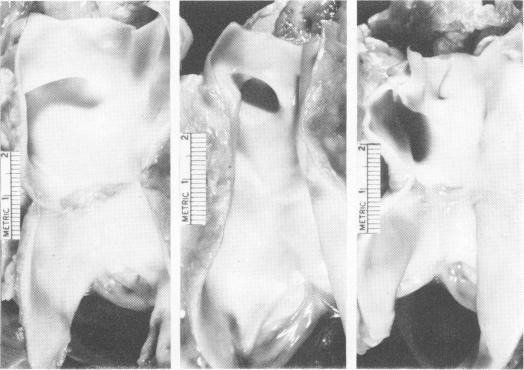

The pulmonary artery lesion after banding: influence of differential materials.

Ann Surg. 1974 May;179(5):805-12. doi: 10.1097/00000658-197405000-00037.